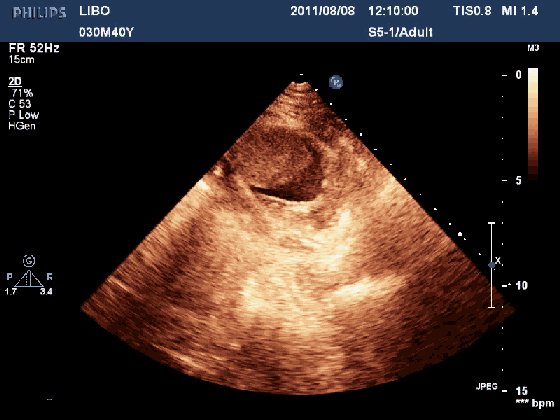

心脏动态图超声